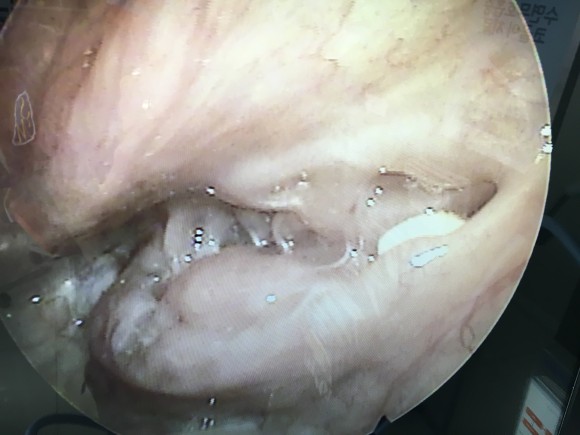

상단:편도와의 윗부분에 결석이 끼여있는 모습과 제거한 편도 결석, 하단:고주파 시술과 PITA 시술 일주일과 3주차의 모습